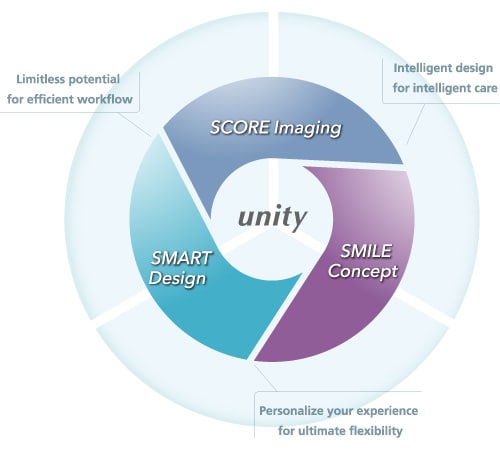

Integrated operating environment encourages efficient workflow

Incorporating "SMART Touch", a customizable touch panel console that enables intuitive operation from the table side as standard.

The new design of the graphic user interface of the main monitor enhances the display of all the essential information during procedures, including system geometric information and X-ray irradiation dose, further improving system workflow.

"Emphasize identification of functions by color"

By changing the button color, you can intuitively operate while concentrating on treatment.